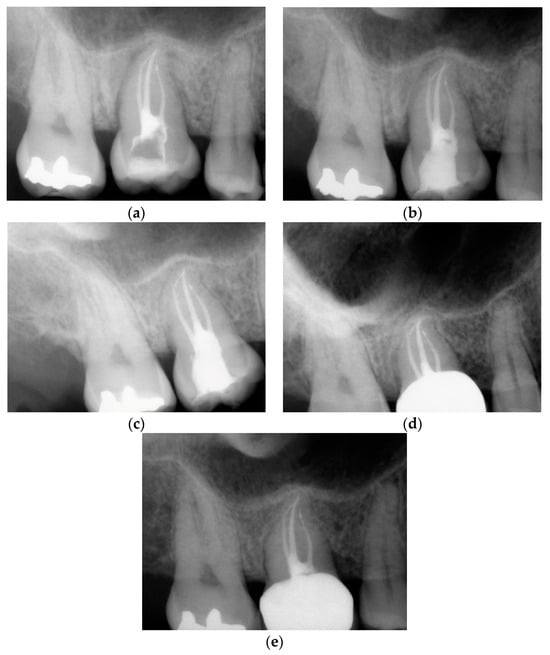

3.2. Case Report